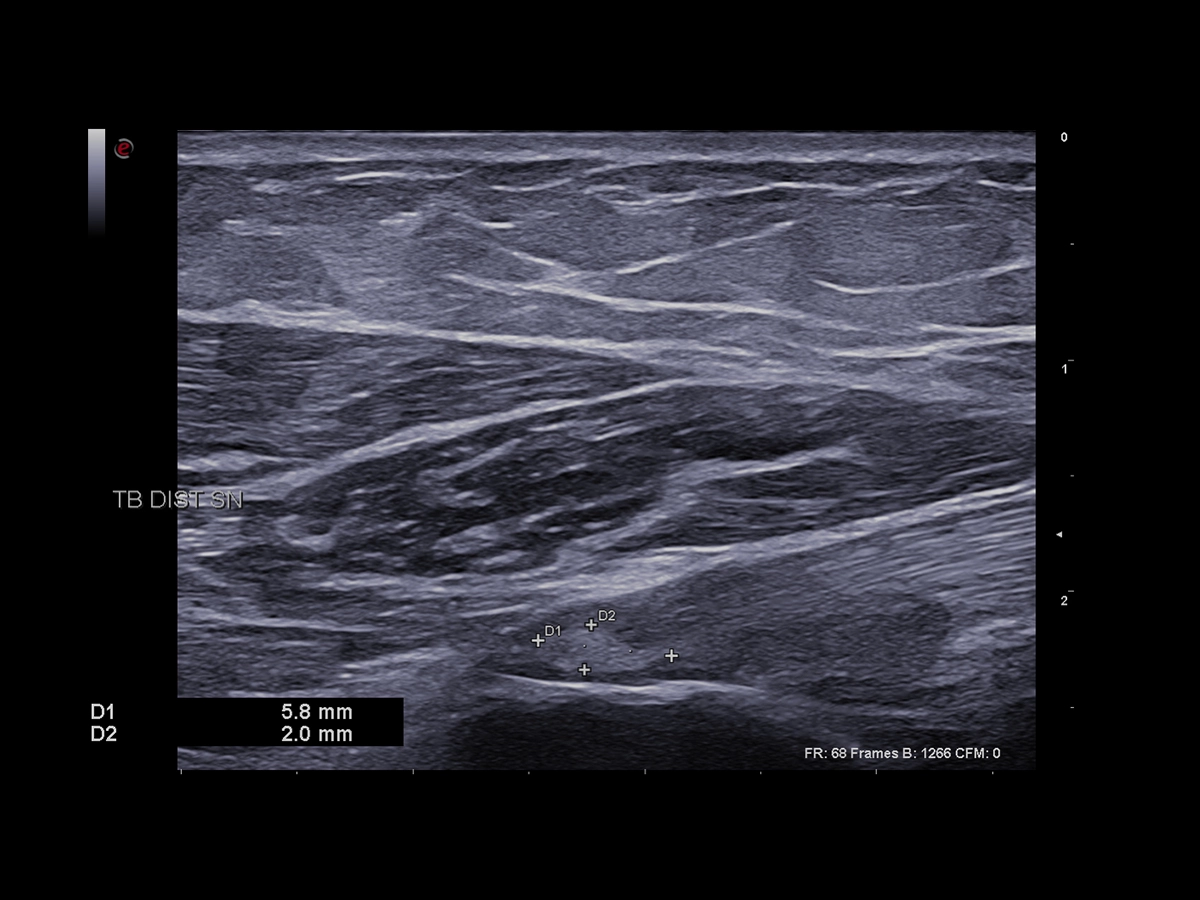

Over the past years, huge improvements in image quality have been achieved, such as broadband transducer technology (up to 25 MHz), harmonic and compound imaging, improved focusing, beam steering, and Power Doppler imaging.

Imaging plays a crucial role in musculoskeletal applications. A genuine technological breakthrough in very superficial explorations, the LMX 4-20, Esaote’s brand-new HD Single Crystal probe, which is operating up to 25 MHz, offers unprecedented clarity even in the smallest details without compromising the deeper areas. Applied to this high-density element per multi-layer matrix structure array, XCrystal Technology enables unparalleled sharp and clear imaging to achieve excellence in superficial ultrasound examinations, and becomes the Esaote gold standard in terms of linear probes.

The use of our latest Very-High Frequency Hockey Stick probe, IHX 6-25, delivers outstanding spatial resolution while facilitating needle access to perform accurate interventional gestures with millimetric precision.